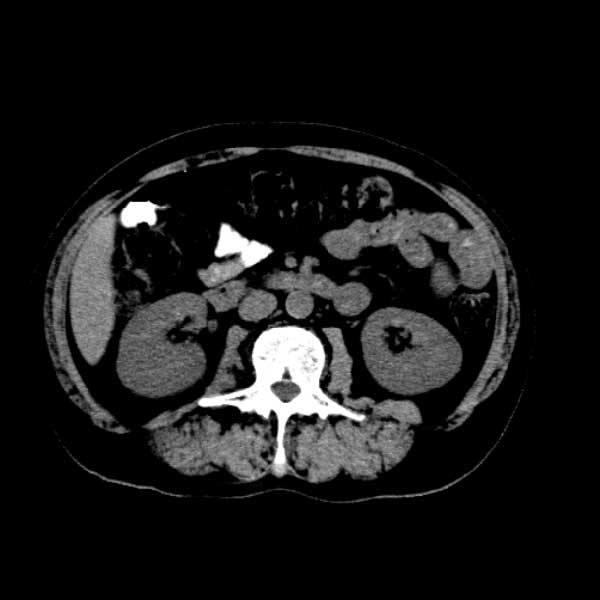

标题: CT13513:男 71 腹部疼痛20余天,近几天高热就诊,骨窗未见异 [打印本页]

标题: CT13513:男 71 腹部疼痛20余天,近几天高热就诊,骨窗未见异

考虑感染性病变可能性大,起源于阑尾?

感染,脓肿形成

考虑为化脓性阑尾炎.脓肿形成.及多肌肉累及.

考虑右侧腰大肌脓肿,向右髂窝、右腹股沟流注。

支持化脓性阑尾炎伴右髂窝脓肿、腰大肌腰方肌脓肿形成。

考虑腹腔及盆腔化脓性炎症,累及右侧髋关节及腹股沟区.

首先考虑化脓性阑尾炎伴腰大肌、腰方肌脓肿,不除外回盲部结核。

回盲部癌待排除。

患者肠镜检查考虑结肠癌,病理证实

患者肠镜检查考虑结肠癌,病理证实。肺部ct可见多发结节,考虑转移